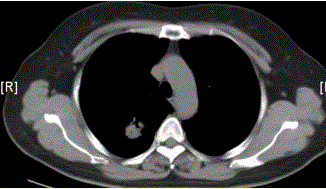

问题 患者女,54岁,无症状,常规体检透视时发现右上肺阴影。既往无结核病史。体格检查阴性。CT结果如下图。 该例最可能诊断为

选项 A.肺结核瘢痕 B.周围型肺癌 C.肺错构瘤 D.肺腺瘤 E.结核球 F.尘肺(硅沉着病)

答案 B

解析 B